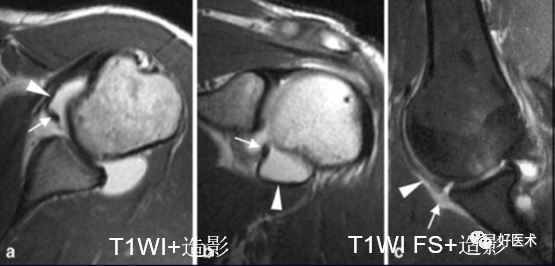

(3)关节腔内造影

脂肪抑制T1WI序列

Gd-DTPA 稀释为1~ 4 :1000 后,注射12. 0~16. 0ml至肩关节腔

MR 关节造影:局限性或弥漫性充满造影剂的裂隙贯穿肌腱全层,肌腱失去其连续性。

6.盂肱韧带肱骨附着部撕脱(HAGL)

关节囊与肱骨交接处不连续;

冠状位上关节囊呈”J”形改变;

T2横轴位肱骨交界处水肿出血;

许多病例合并Hill-Sachs损伤。

少见,多发生于橄榄球、冰上运动等接触性体育的运动员,只能依靠关节造影发现。